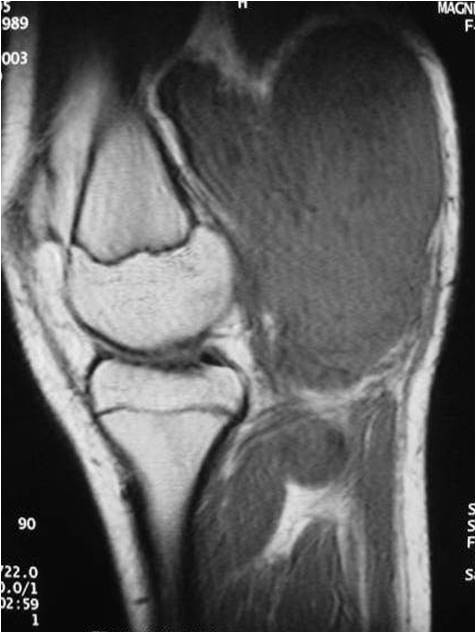

Radiographic Presentation

- Aggressive motheaten to permeative lesion

- Indistinct border in most cases

- Osseous destruction with a soft tissue component

- Chondroid matrix calcification may be present (60-70% of cases)

- Soft tissue mass